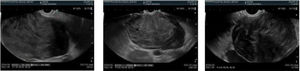

Echoendoscopy (Fig. 2) identified an exophytic, hypoechoic, well-delineated subepithelial lesion dependent on the muscle layer of the duodenal wall, measuring approximately 10 × 7 cm, that was highly suspected to be a gastrointestinal stromal tumor (GIST). A fine-needle puncture (FNP) was performed and immunohistochemistry revealed diffuse, intense positivity for desmin and caldesmon, the absence of typical GIST markers (CD117, DOG-1), and negative CD34, S100, and CKAE1-AE3. The mitotic index of 3–4 mitosis/mm² and high Ki-67 reinforced the suspicion of a smooth muscle tumor.